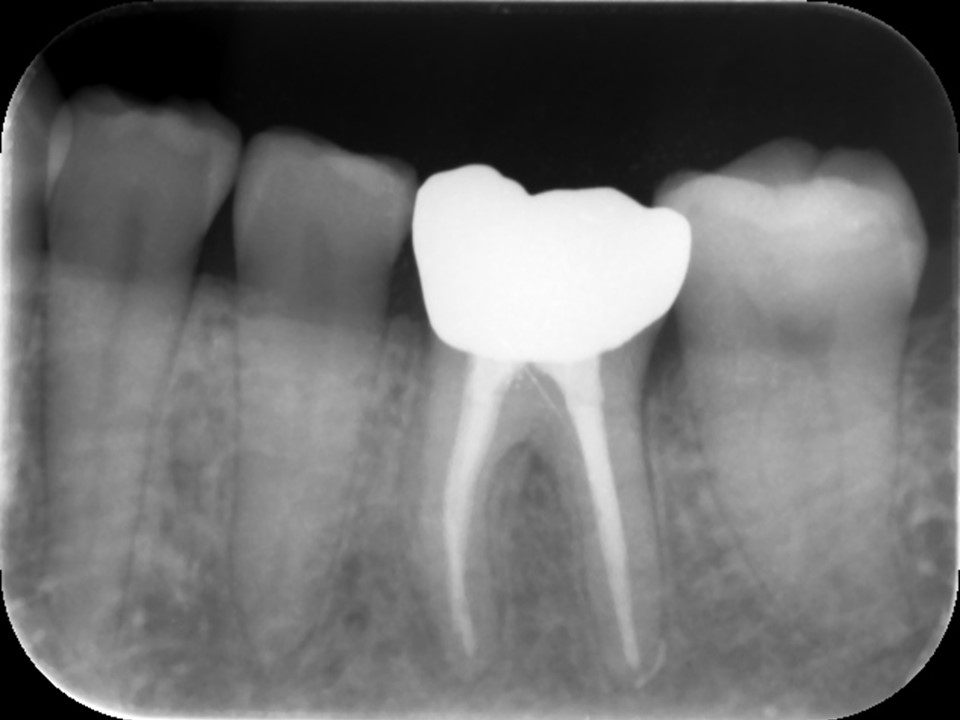

| 治療後レントゲン | 治療後CT |

|---|---|

| 治療後レントゲン |

|---|

| 治療後CT |

感染根管治療10か月後のレントゲンおよびCT画像です。

根尖病変は消失し、歯槽骨は完全な再生を認め治癒しています。